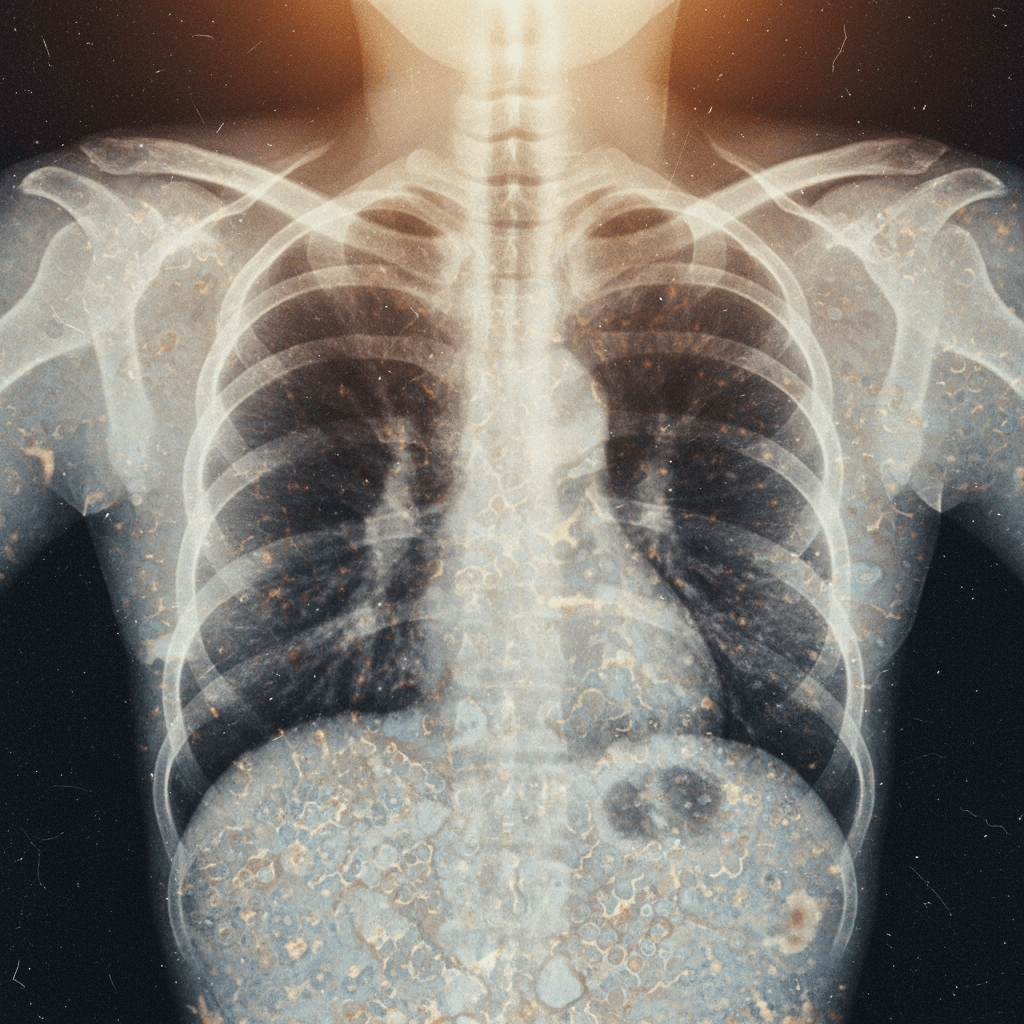

Patients with systemic sclerosis, already vulnerable due to immunosuppression and lung involvement, face a heightened risk of pulmonary tuberculosis. This case highlights the diagnostic and therapeutic challenges when TB mimics or masks ILD progression.

Patients with systemic sclerosis (SSc) face an elevated risk of opportunistic infections, particularly pulmonary tuberculosis (TB), especially in high-burden countries. This case highlights the need for heightened surveillance and tailored screening strateg...